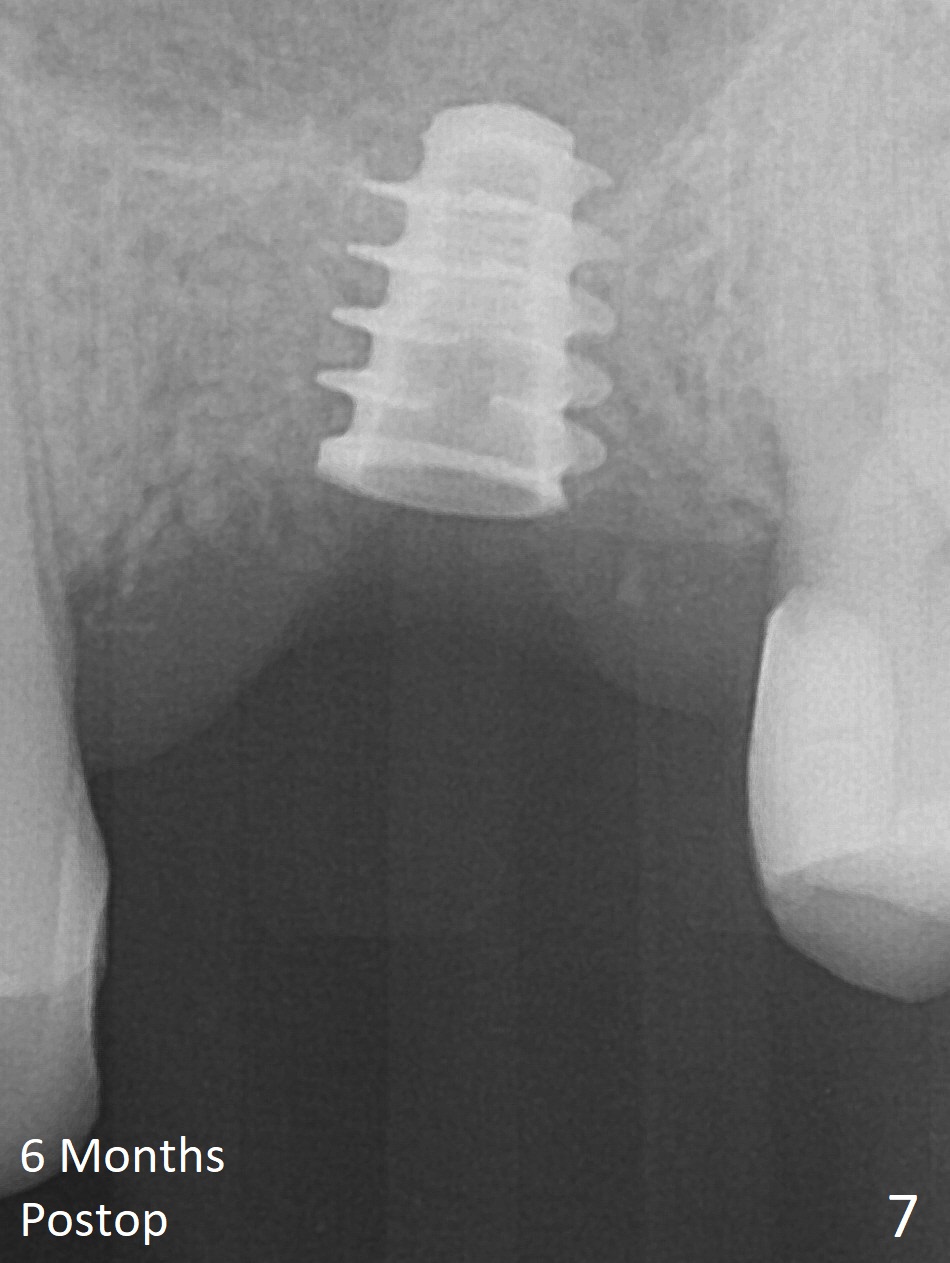

The implant is mobile 4 months postop (Fig.6).  A 6x2 mm healing abutment is placed next.  Although the implant remains mobile 6 months postop, the bone seems to have become denser around the implant (Fig.7-9).  A healing screw is placed.  When the bone height is limited (<7 mm), place a larger implant (>5.5 mm).  The implant seems to have osteointegrated 8 months postop (Fig.10).  Impression is taken following placing a 6.5x4(3) mm abutment.  The patient reports pain after cementation, which is less when the abutment screw is loose (9.5 months postop, 2 weeks post cementation).  CBCT taken after placement of a healing screw apparently shows loose bone mesial and distal to the implant (Fig.11 *).  The implant trajectory is less favorable.  It seems necessary to change to a large implant with more sold threads (Fig.12).